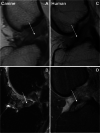

Canine ACL rupture: a spontaneous large animal model of human ACL rupture

Background: Anterior cruciate ligament (ACL) rupture in humans is a common condition associated with knee pain, joint instability, and secondary osteoarthritis (OA). Surgical treatment with an intraarticular graft provides reasonable outcomes at mid and long-term follow-up. Non-modifiable and modifiable factors influence risk of ACL rupture. The etiology, mechanobiology, causal biomechanics, and causal molecular pathways are not fully understood. The dog model has shared features of ACL rupture that make it a valuable spontaneous preclinical animal model. In this article, we review shared and contrasting features of ACL rupture in the two species and present information supporting spontaneous canine ACL rupture as a potentially useful preclinical model of human ACL rupture with a very large subject population.

Results: ACL rupture is more common in dogs than in humans and is diagnosed and treated using similar approaches to that of human patients. Development of OA occurs in both species, but progression is more rapid in the dog, and is often present at diagnosis. Use of client-owned dogs for ACL research could reveal impactful molecular pathways, underlying causal genetic variants, biomechanical effects of specific treatments, and opportunities to discover new treatment and prevention targets. Knowledge of the genetic contribution to ACL rupture is more advanced in dogs than in humans. In dogs, ACL rupture has a polygenetic architecture with moderate heritability. Heritability of human ACL rupture has not been estimated.